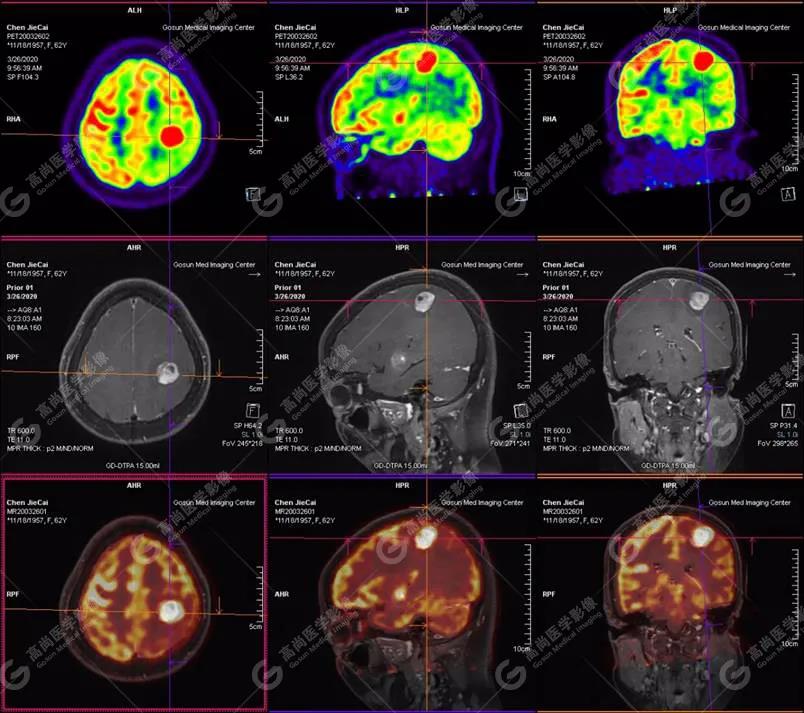

【廣東高尚醫(yī)學影像】多模態(tài)影像|顱內(nèi)淋巴瘤PET-MR融合顯像1例

左側(cè)顳葉、頂葉、左側(cè)基底節(jié)區(qū)及胼胝體部多發(fā)結(jié)節(jié)狀高代謝病灶,部分合并囊變、出血,MR平掃+增強示不均勻輕、中度強化,綜合考慮為顱內(nèi)原發(fā)惡性腫瘤,以淋巴瘤可能性大

彌漫大B細胞淋巴瘤

淋巴瘤病變多位于中線兩旁的深部腦實質(zhì)、側(cè)腦室周圍及腦表面,甚少累及腦膜和顱骨,幕上多于幕下,呈分葉狀或握拳狀,水腫及占位效應較輕,部分病灶內(nèi)可見囊變、出血及其邊緣的硬環(huán)征、尖角征、臍凹征,增強掃描呈現(xiàn)的“臍凹征或者“握拳征”是淋巴瘤較為特征性的一個表現(xiàn)。

18F-FDG PET PET顯像中呈明顯高代謝病灶。

顱內(nèi)惡性淋巴瘤對18F-FDG的攝取率很高,一般SUV在5~10以上,18F-FDG PET顯像中攝取明顯高于正常腦皮層,因此具有特征性。

PET/CT-MR檢查是原發(fā)顱內(nèi)惡性淋巴瘤的重要檢查方法,能有效提高診斷正確率;在早期發(fā)現(xiàn)、準確分期、放化療后檢測具有極重要的作用。